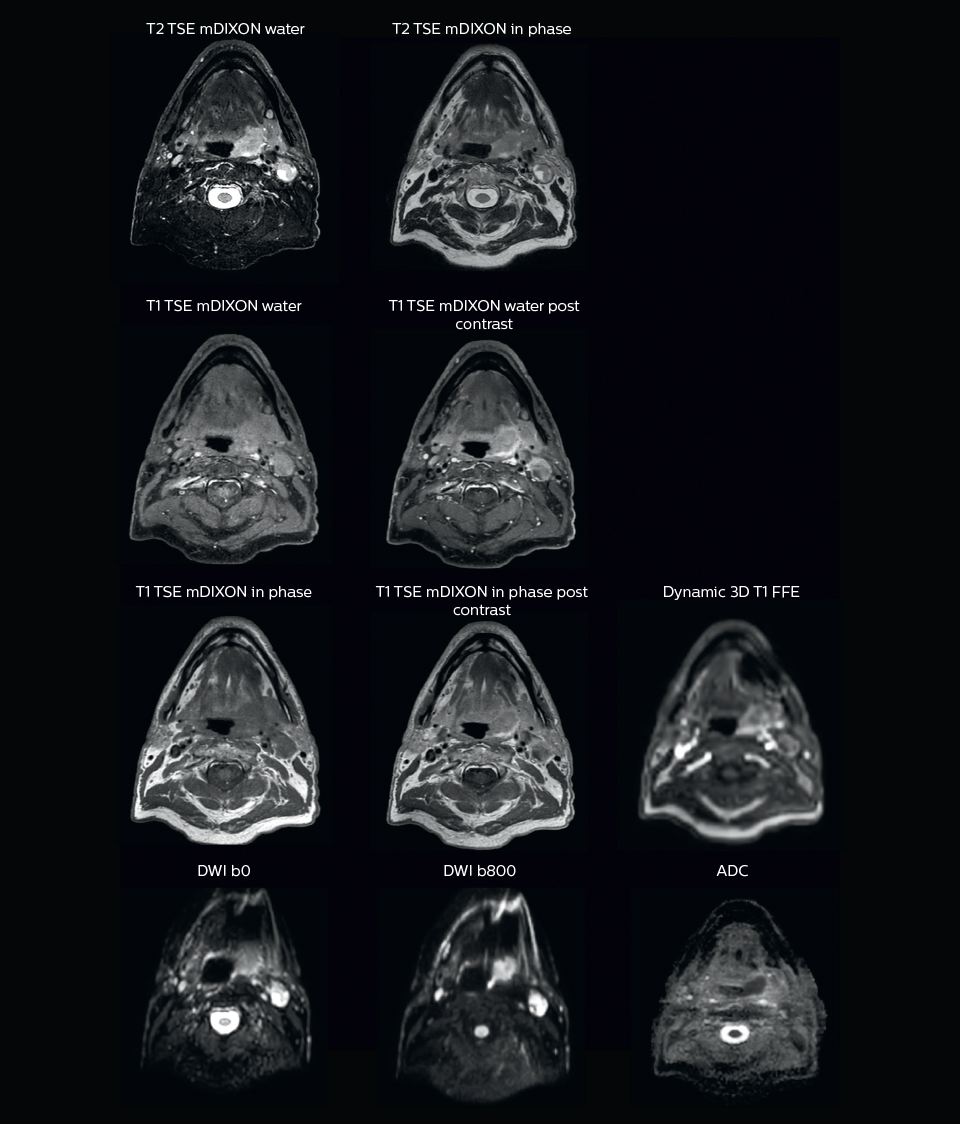

“MRI can provide anatomical and functional information. The most important sequence for tumor delineation is the T1-weighted scan after contrast administration. On post-contrast T1-weighted MR images with fat suppression, the tumor can be distinguished due to its high perfusion and leaky vessels. We also use pre-contrast T1- weighted images, which show tumor extension into the fatty tissue.

“On the T2-weighted MRI with fat suppression the tumor with its edematous surrounding tissue can be clearly distinguished. This is particularly useful if the tumor does not show enhancement after contrast injection.

“Diffusion weighted imaging (DWI) shows very high contrast between the tumor and surrounding tissue. DWI helps us to see how a tumor extends into another structure, which we may not see on the T1-weighted or T2-weighted images. However, as DWI images are prone to distortions, these are mainly used to visualize the tumor and for response assessment, and not yet so much for delineation. I like to include diffusion weighted imaging, as it is so easy to see the tumor in these images. In my opinion, it has great potential, both for supporting tumor delineation and in response assessment.”

“We use pre- and post-contrast T1- and T2-weighted sequences with the fast and robust mDIXON method for fat suppression,” says Dr. Philippens. “Dynamic contrast-enhanced imaging is performed with high temporal resolution and low spatial resolution, to see the contrast agent uptake in the tumor. Diffusion weighted imaging is used qualitatively to see how the tumor extends into another structure, rather than for strict delineation.”